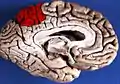

![]() Medial surface of left cerebral hemisphere. (Precuneus visible at top left.) (Anterior to the right.) | |

Precuneus of left cerebral hemisphere (shown in red).

Medial surface of left cerebral hemisphere. (Precuneus visible at top left.)